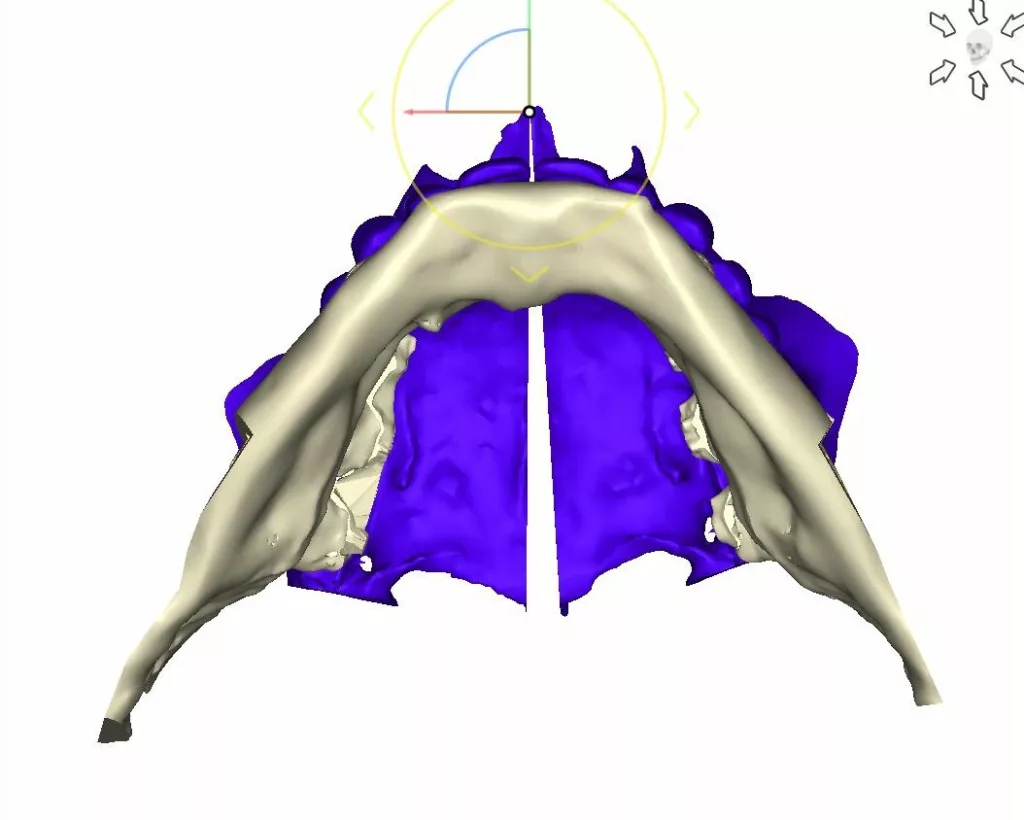

L’ostéotomie de Lefort 1 permet de déplacer la totalité du maxillaire supérieur c’est à dire l’ensemble « os basal – os alvéolaire – dents supérieures » dans les 3 dimensions de l’espace.

L’ostéotomie de Lefort 1 peut aussi être réalisée en un, en deux fragments ou en trois fragments pour permettre une mobilisation différente pour chacun des fragments du maxillaire. Il peut s’agir d’une expansion transversale lorsque le maxillaire est trop étroit transversalement. Il peut s’agir de mouvements spécifiques pour chacun des fragments maxillaires comme cela est souvent nécessaire en cas d’asymétrie ou de béance.